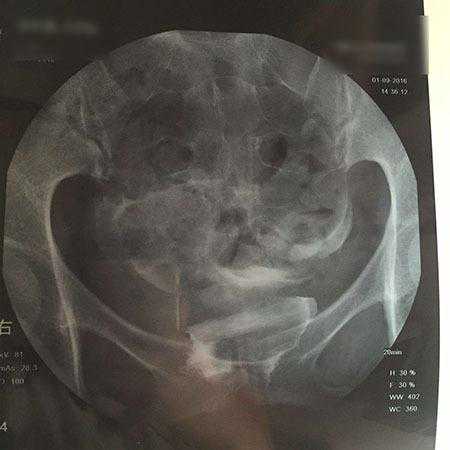

最常见的是月经量越来越少,乃至闭经,身体过瘦或过度肥胖,不能正常排卵,或卵子质量差。